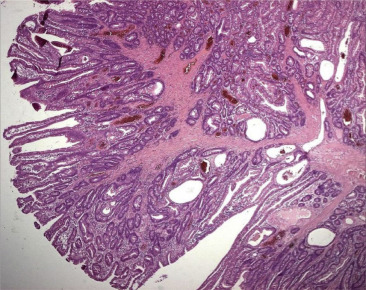

A 28-year-old man without any underlying disease presented with dizziness and general malaise for 6 months. He came to the clinic for help initially. Vital signs and physical examination were normal. Blood tests revealed only the following abnormality: hemoglobin 8.6 g/dL. His fecal occult blood test result was positive. Esophagogastroduodenoscopy and colonoscopy showed nonspecific findings. Ferrous sulfate was prescribed for suspected iron-deficiency anemia. Owing to refractory anemia, he was transferred to our hospital for further evaluation. Small bowel series showed a jejunal polypoid lesion with increasing folds and lumen dilatation in the jejunum (Fig. 1 ). Computed tomography of abdomen and pelvis showed soft tissue mass (4.8 cm × 2.5 cm) within a proximal jejunal loop and intussusception of jejunal loops (Fig. 2 , yellow arrow). This patient received surgical resection. A long-stalk mass (about 4 cm in size) at the proximal jejunum, 25 cm distal to the Treit'z ligament (Fig. 3 ), was found during the operation, and this tumor caused intussusception of the jejunum. After surgery, his anemia improved gradually and he was well until recently.

Jejunal polypoid lesion (red arrow) with increasing folds and lumen dilatation ...

Jejunal polypoid lesion (red arrow) with increasing folds and lumen dilatation (yellow arrow).

Figure 1.